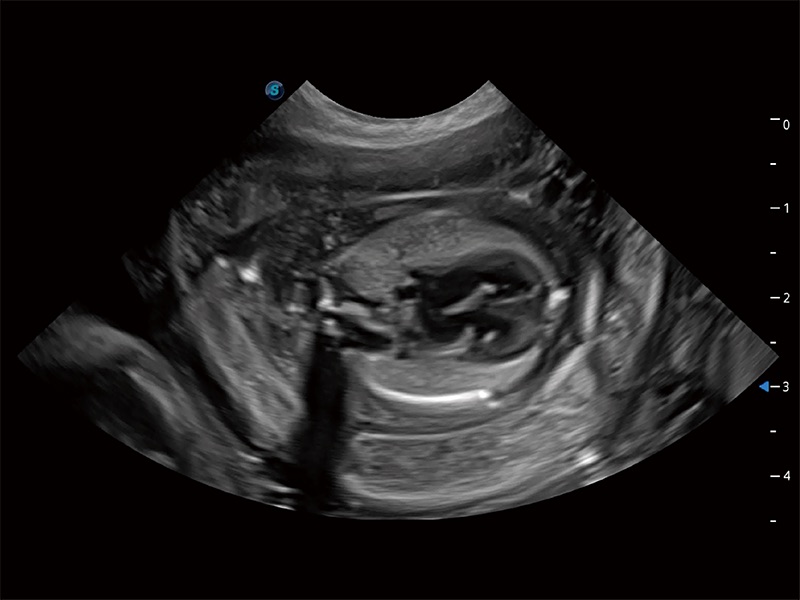

动物是人类最亲密的朋友和最值得信赖的伙伴。狗万官方网站也一直致力于探索动物专用的超声影像解决方案。全新推出的ProPet系列,是狗万官方网站在动物超声影像智能化、专业化、精准化的一次跨越式革新。动物不能用言语来表述自己的不适,通过超声影像,ProPet系列搭建了动物医生与不同物种沟通的“桥梁”,为动物医生注入了“治愈之力”。 ProPet 80 是狗万官方网站匠心打造的一款高端动物专用彩超,采用性能卓越的全新硬件架构,极大提升超声系统的运行效率和数据处理能力,帮助动物医生从容应对日益增多的挑战性病例和日益多样化的临床需求。

高性能和先进的临床应用工具可以为动物医生提供临床信心。ProPet 80 搭载了先进的腹部和浅表应用工具,帮助医生在日常临床实践中发挥前所未有的作用。

ProPet 80 全新的动物超声智能软件和丰富的探头群,为动物医生提供了高清晰度和精细分辨率的图像,无论在宠物、马科、畜牧还是实验室动物等应用中都可以轻松应对,为您的日常工作带来满意的体验。